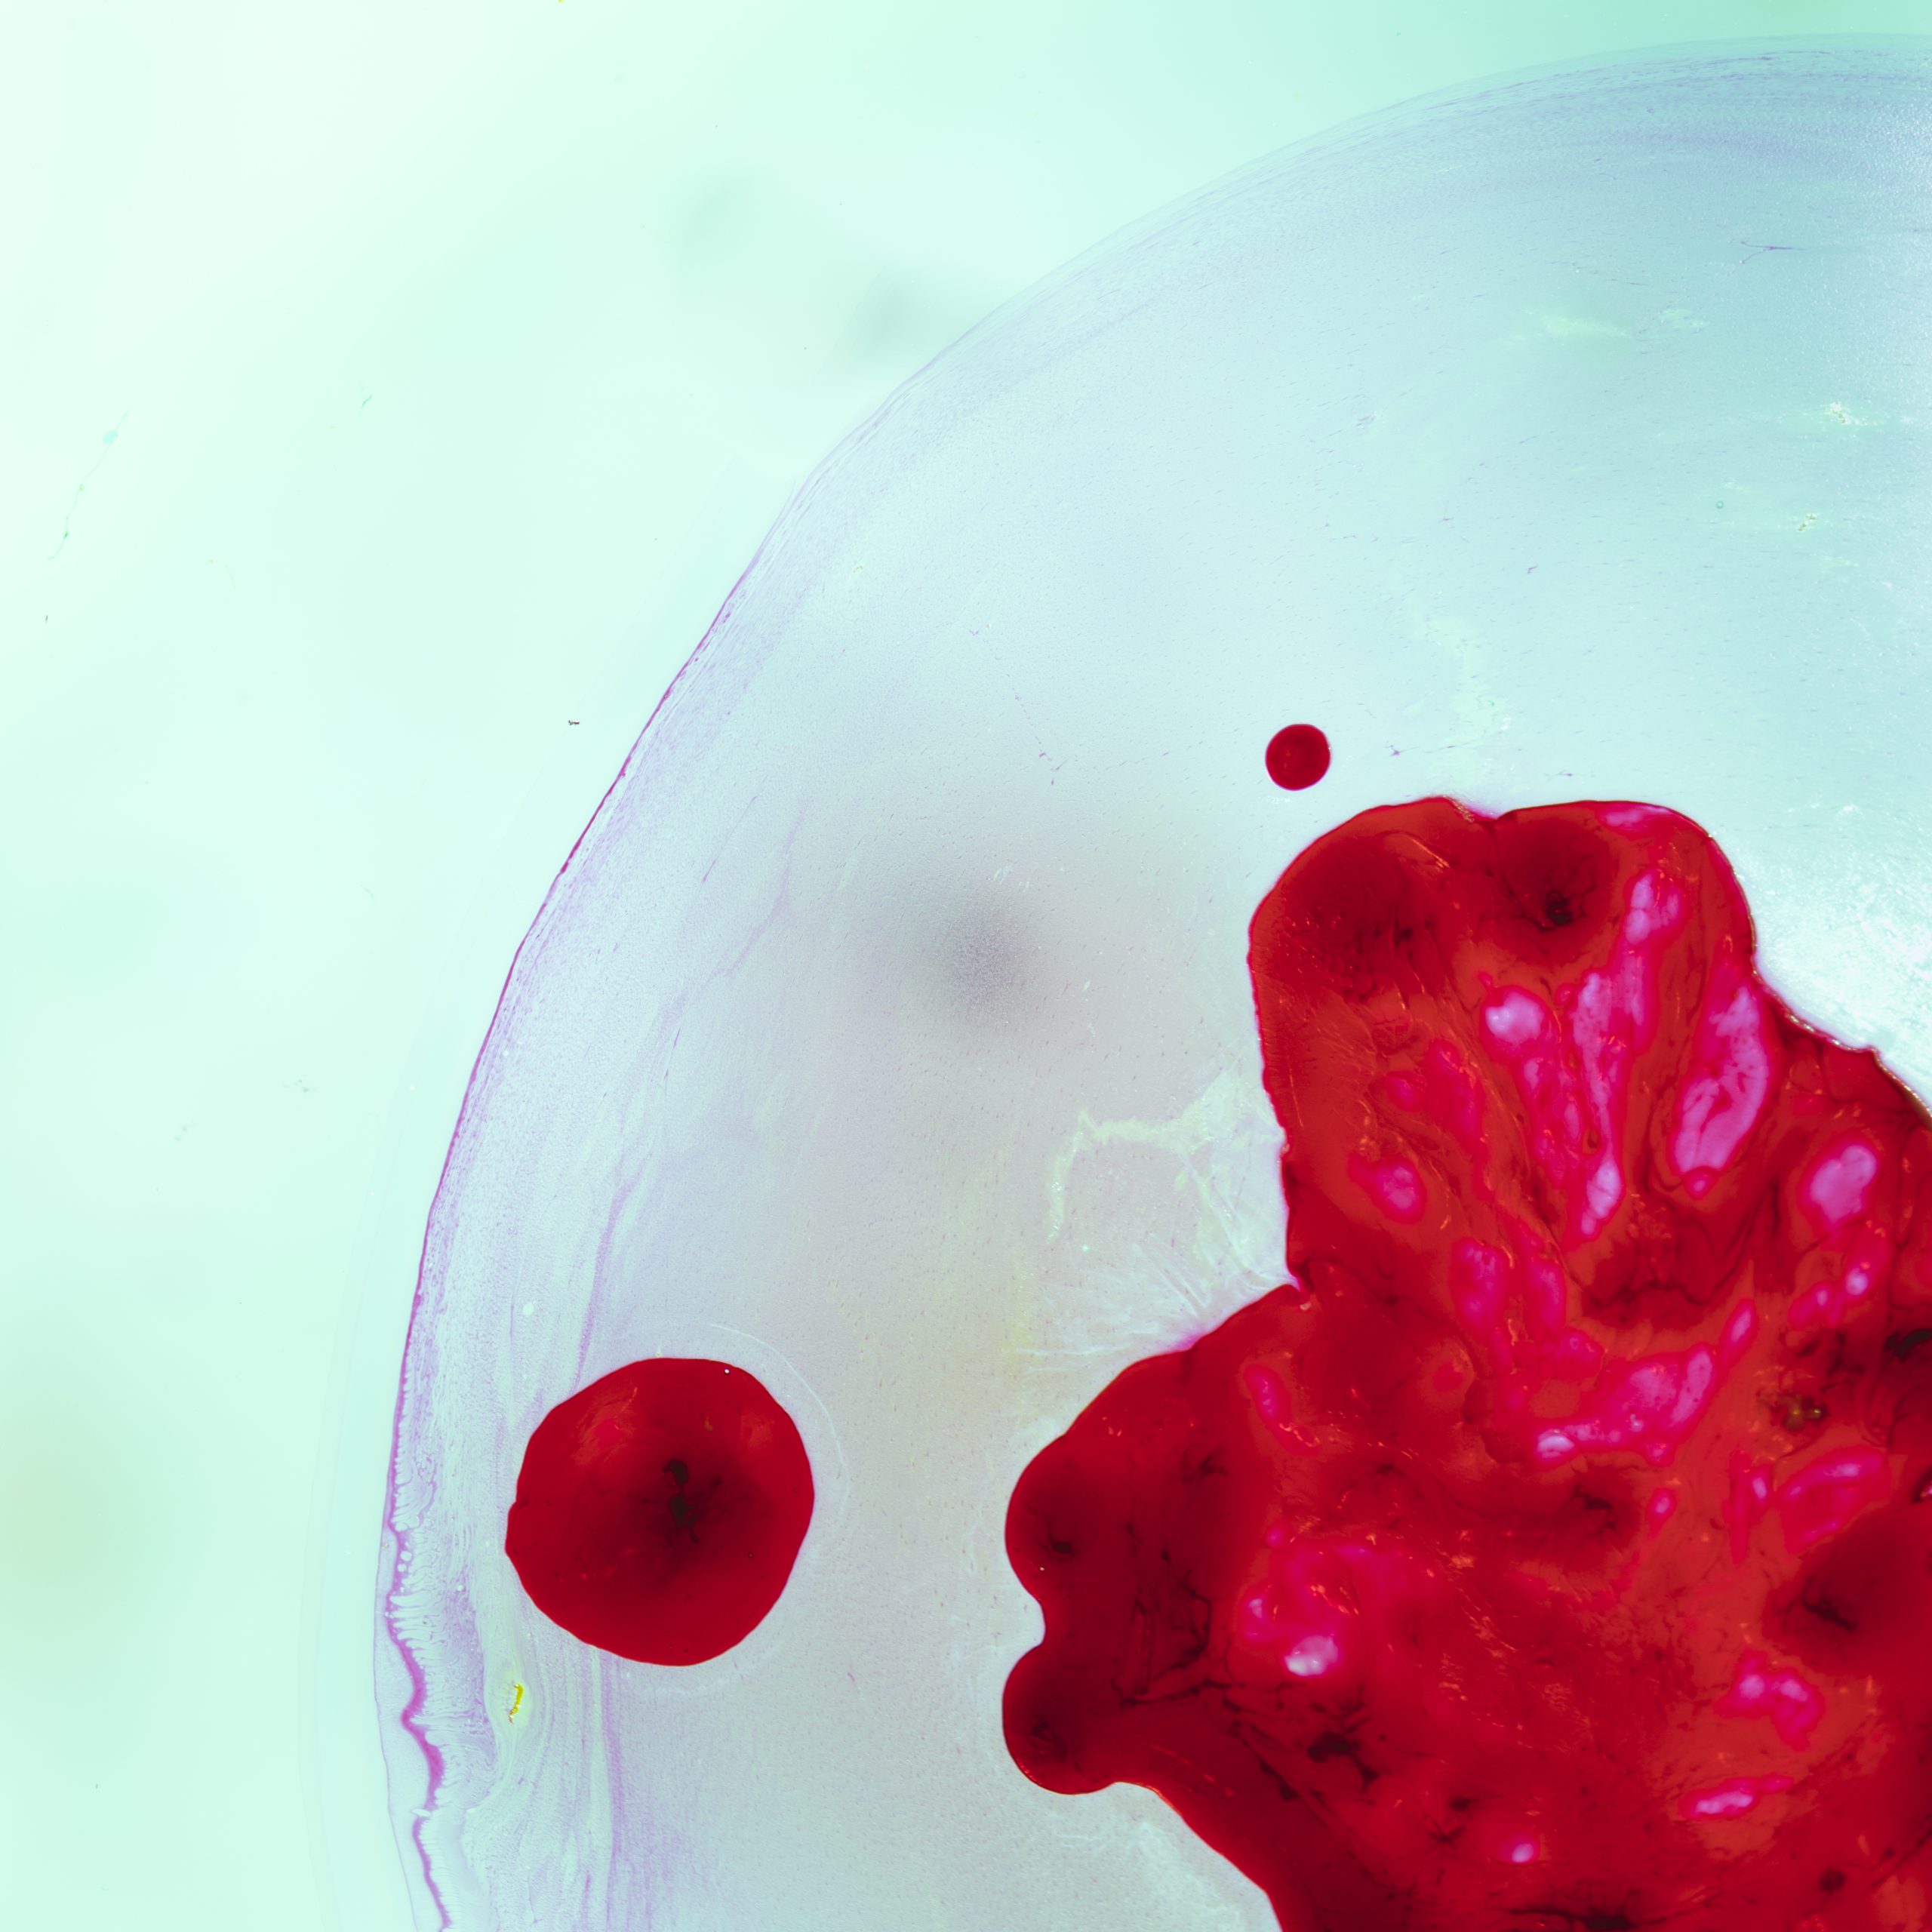

image is to be replaced’